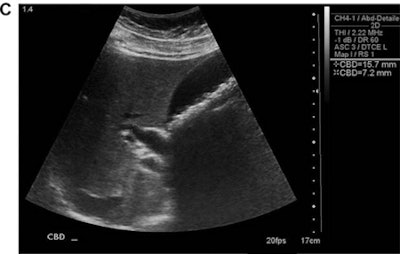

The conventional ultrasound studies were performed by sonographers certified by the American Registry for Diagnostic Medical Sonographers (ARDMS) on an HD-5000 (Philips Healthcare), IU-22 (Philips), E-8 (GE Healthcare), or Antares (Siemens Healthineers) scanner. The study's senior author, Dr. Robert Harris, read the exams immediately after they were performed; these interpretations served as the reference diagnostic standard and were confirmed or modified one year after patient enrollment based on further clinical evaluation and follow-up, laboratory/pathologic data, and additional imaging studies. Harris, who has 23 years of general ultrasound experience and 10 years of compact ultrasound experience, then performed all point-of-care ultrasound studies using a SonoSite 180 Plus scanner (Fujifilm SonoSite). The point-of-care exams were targeted, focused exams that took two to three minutes to perform.